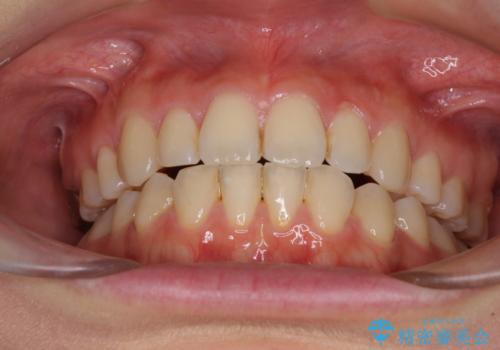

抜歯矯正を行ったことで、デコボコが改善されただけでなく、口元も下がったことで口が閉じやすくなりました。